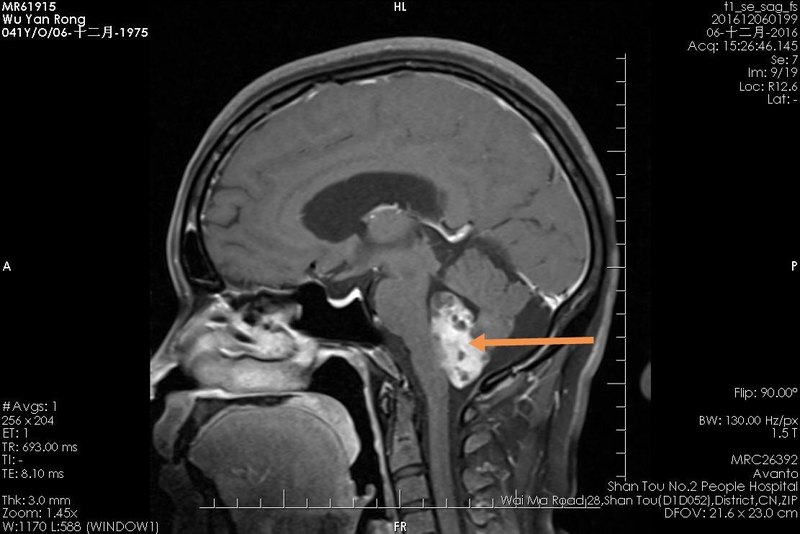

女性患者,58歲,因“右耳聽力下降并頭暈不適半年余,”入院。 查體:右耳聽力明顯下降,右側(cè)肢體共濟障礙。 診斷:聽神經(jīng)鞘瘤 術(shù)前核磁共振檢查如下面: 手術(shù)方法:右乙狀竇后入路聽腫瘤切除術(shù) 患者麻醉成功后,取左側(cè)臥位,頭略低位,右側(cè)乳突根位于最高點,取枕下乙狀竇后入路,電動顱鉆鉆1孔,銑刀銑下骨瓣3.0cmX2.5cm。剪開硬腦膜,顯露小腦半球及橋小腦角區(qū),切開蛛網(wǎng)膜釋放腦脊液,腦組織塌陷良好。用動態(tài)無牽拉技術(shù),顯露橋小腦角,見腫瘤組織,質(zhì)地較韌,血供較豐富,三叉神經(jīng)、面神經(jīng)、聽神經(jīng)、舌咽神經(jīng)均受累及,與腦干粘連緊密。首先囊內(nèi)切除腫瘤,保留薄層腫瘤壁;磨開內(nèi)聽道,將腫瘤自面神經(jīng)上切除,腫瘤完全切除。 術(shù)后病人恢復(fù)好,輕面癱,眼瞼可閉合;有部分聽力殘存。 術(shù)后第一天復(fù)查核磁共振,腫全切除,如下圖: 點評:該病例腫瘤巨大,嚴重擠壓腦干、小腦,手術(shù)難度、風(fēng)險大,手術(shù)成功切除腫瘤,無嚴重后遺癥。